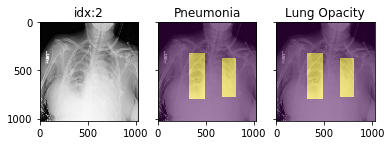

'Support Devices': {0.0: 21757, 1.0: 99747}}Pathology masks (demo notebook)

Masks are available in the following datasets:

xrv.datasets.RSNA_Pneumonia_Dataset() # for Lung Opacity

xrv.datasets.SIIM_Pneumothorax_Dataset() # for Pneumothorax

xrv.datasets.NIH_Dataset() # for Cardiomegaly, Mass, Effusion, ...Example usage:

d_rsna = xrv.datasets.RSNA_Pneumonia_Dataset(imgpath="stage_2_train_images_jpg",

views=["PA","AP"],

pathology_masks=True)

# The has_masks column will let you know if any masks exist for that sample

d_rsna.csv.has_masks.value_counts()

False 20672

True 6012

# Each sample will have a pathology_masks dictionary where the index

# of each pathology will correspond to a mask of that pathology (if it exists).

# There may be more than one mask per sample. But only one per pathology.

sample["pathology_masks"][d_rsna.pathologies.index("Lung Opacity")]it also works with data_augmentation if you pass in data_aug=data_transforms to the dataloader. The random seed is matched to align calls for the image and the mask.